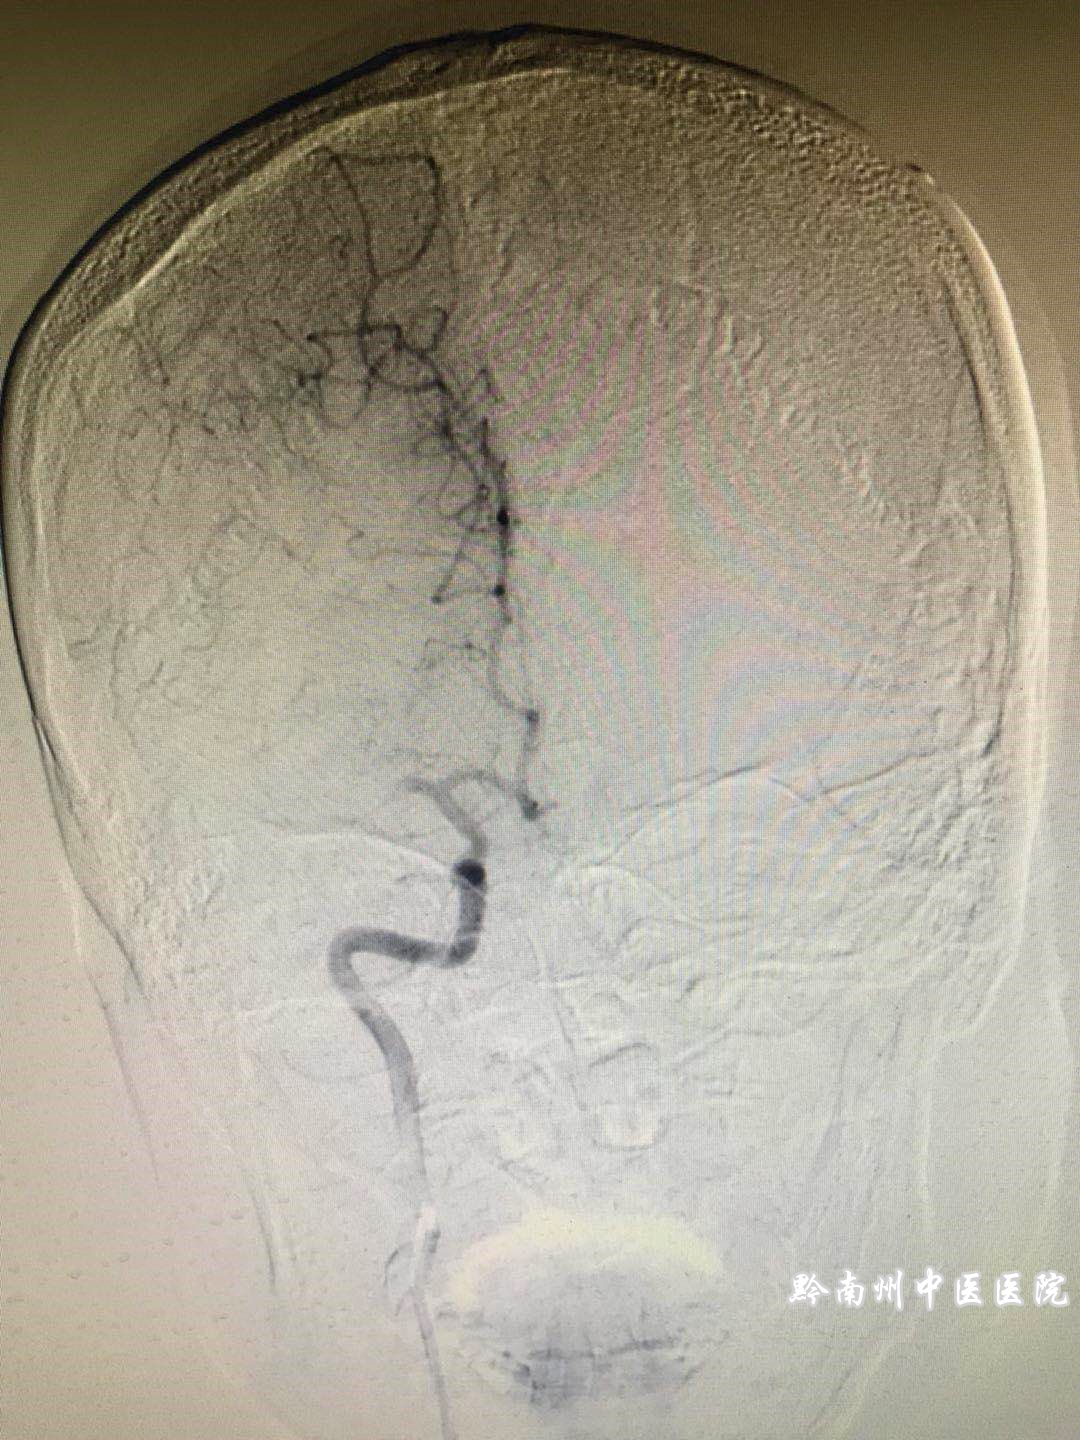

1时50分:造影见大脑中动脉显影好,手术顺利。结束返回病房。

8时30分复查头颅CT未见颅内出血、患者神清、左侧肢体肌力3级,家属满意。